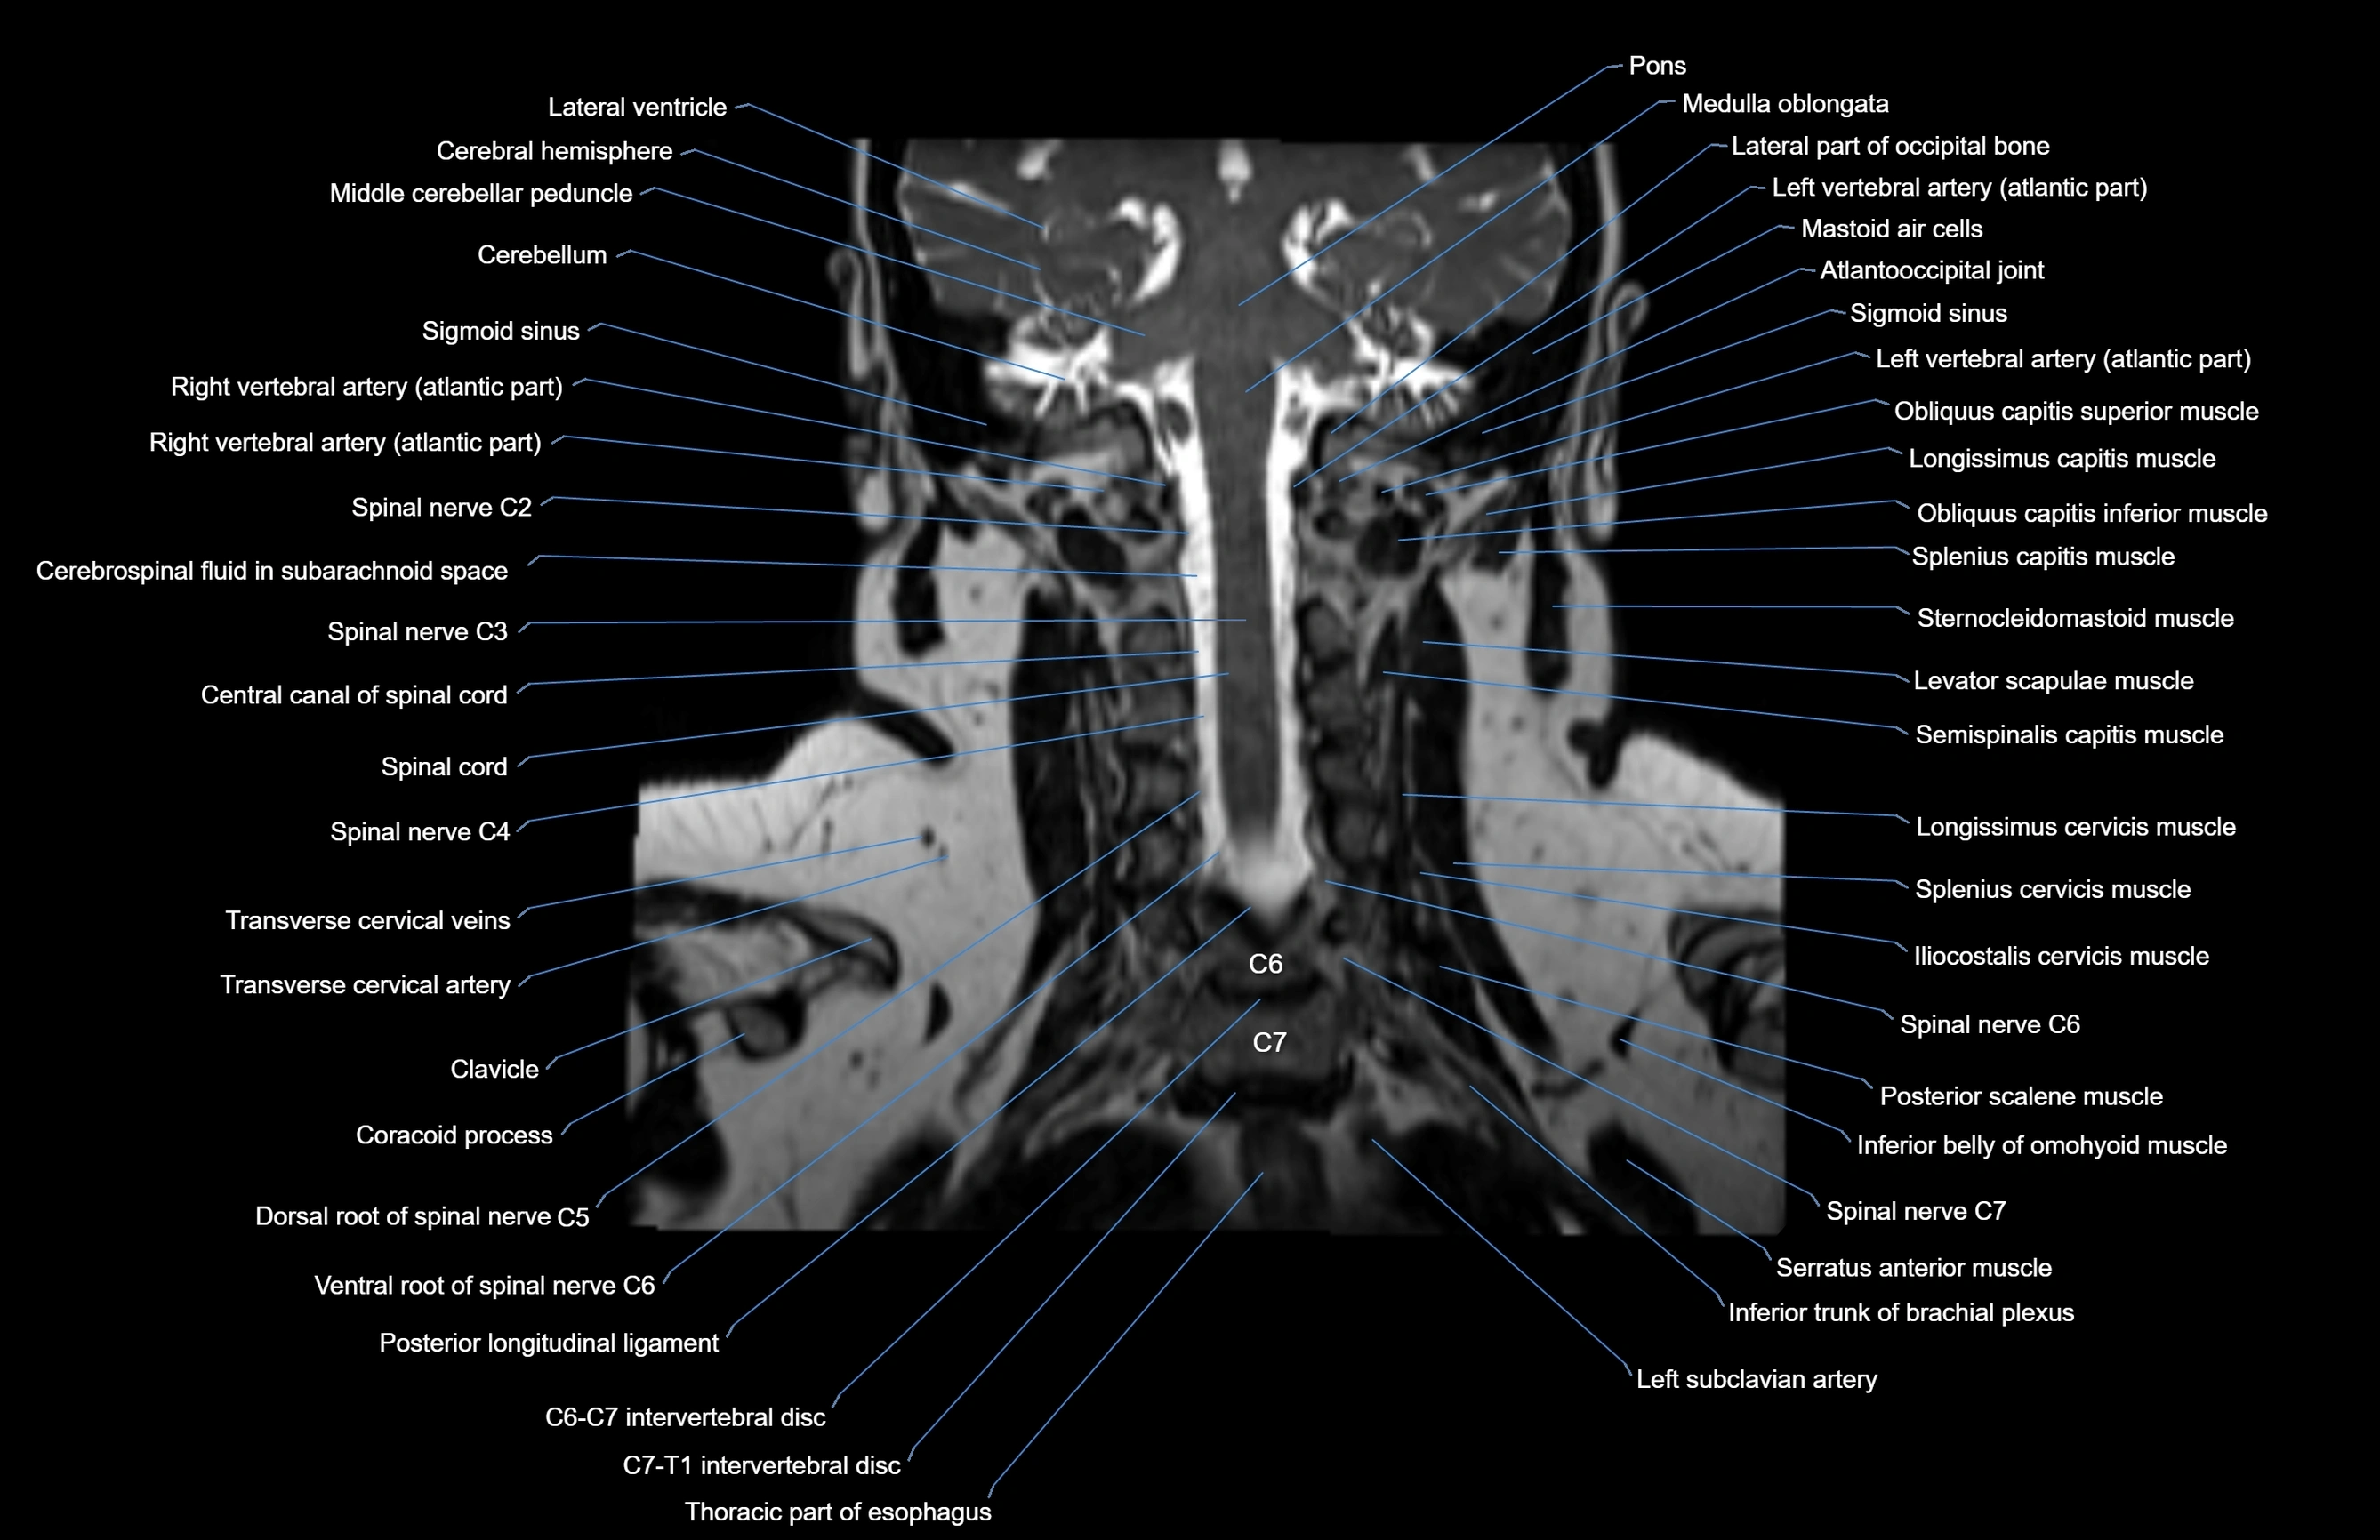

- Cerebellum

- Middle cerebellar peduncle

- Spinal cord

- Cervical spinal nerve 2 (C2)

- Cervical spinal nerve 3 (C3)

- Cervical spinal nerve 4 (C4)

- Cervical spinal nerve 6 (C6)

- Cervical spinal nerve 7 (C7)

- Left vertebral artery (atlantic part)

- Left vertebral artery (cervical part)

- Right vertebral artery (atlantic part)